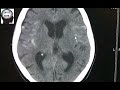

クモ膜下出血の画像診断(脳底動脈瘤破裂)【画像診断チャンネル】

脳底動脈瘤破裂に伴うSAH、血腫の部位から破裂部位を推測しよう。 →http://wp.me/p3Jsrl-3xA ▷救急画像診断を中心に、CT,MRI画像診断、画像の読み方を解説しています。 http://xn--o1qq22cjlllou16giuj.jp/